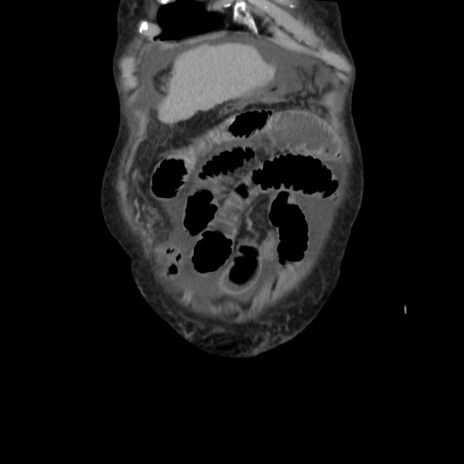

矢状断像

【症例】80歳代 女性

【主訴】腹部膨満感

【現病歴】他院にて肝硬変にてフォロー中。1週間前から便秘、腹部膨満感、臍部腫瘤あり受診となる。

【既往歴】肝硬変

【身体所見】腹部膨隆あり、皮膚変化なし、疼痛なし。

【データ】WBC 4600、CRP 0.25